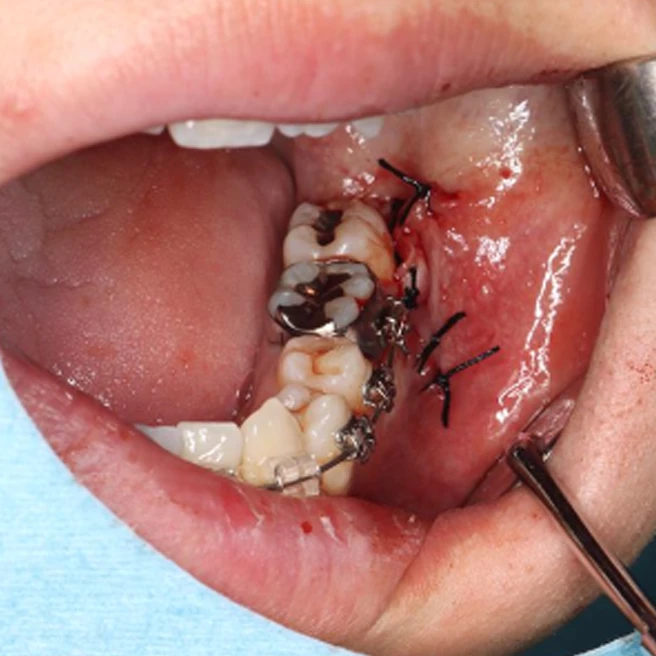

埋まっている親不知の周りの骨を削り出し、歯を分割して抜いていくことになります。当然抜歯後は穴が開き、そこに血液がたまり、線維状になり、骨化していくことで治癒します。その肉になる過程で痛み止めを服薬していくことになるのですが、通常の飲むタイプの痛み止めですと胃で分解吸収され、全身にいきわたってしまうため、患部に作用する鎮痛成分は飲む量に比べて非常に僅かな量なのです。

そこで我々は独自に開発した水に溶けにくいゲル状の鎮痛剤を患部に入れ、鎮痛成分を少しずつ患部に直接作用するような開発を行っています。口から飲んで胃で吸収するのに比べ、100分の1の量の成分で効果があり、また効果時間も非常に長くなることが確認されています。